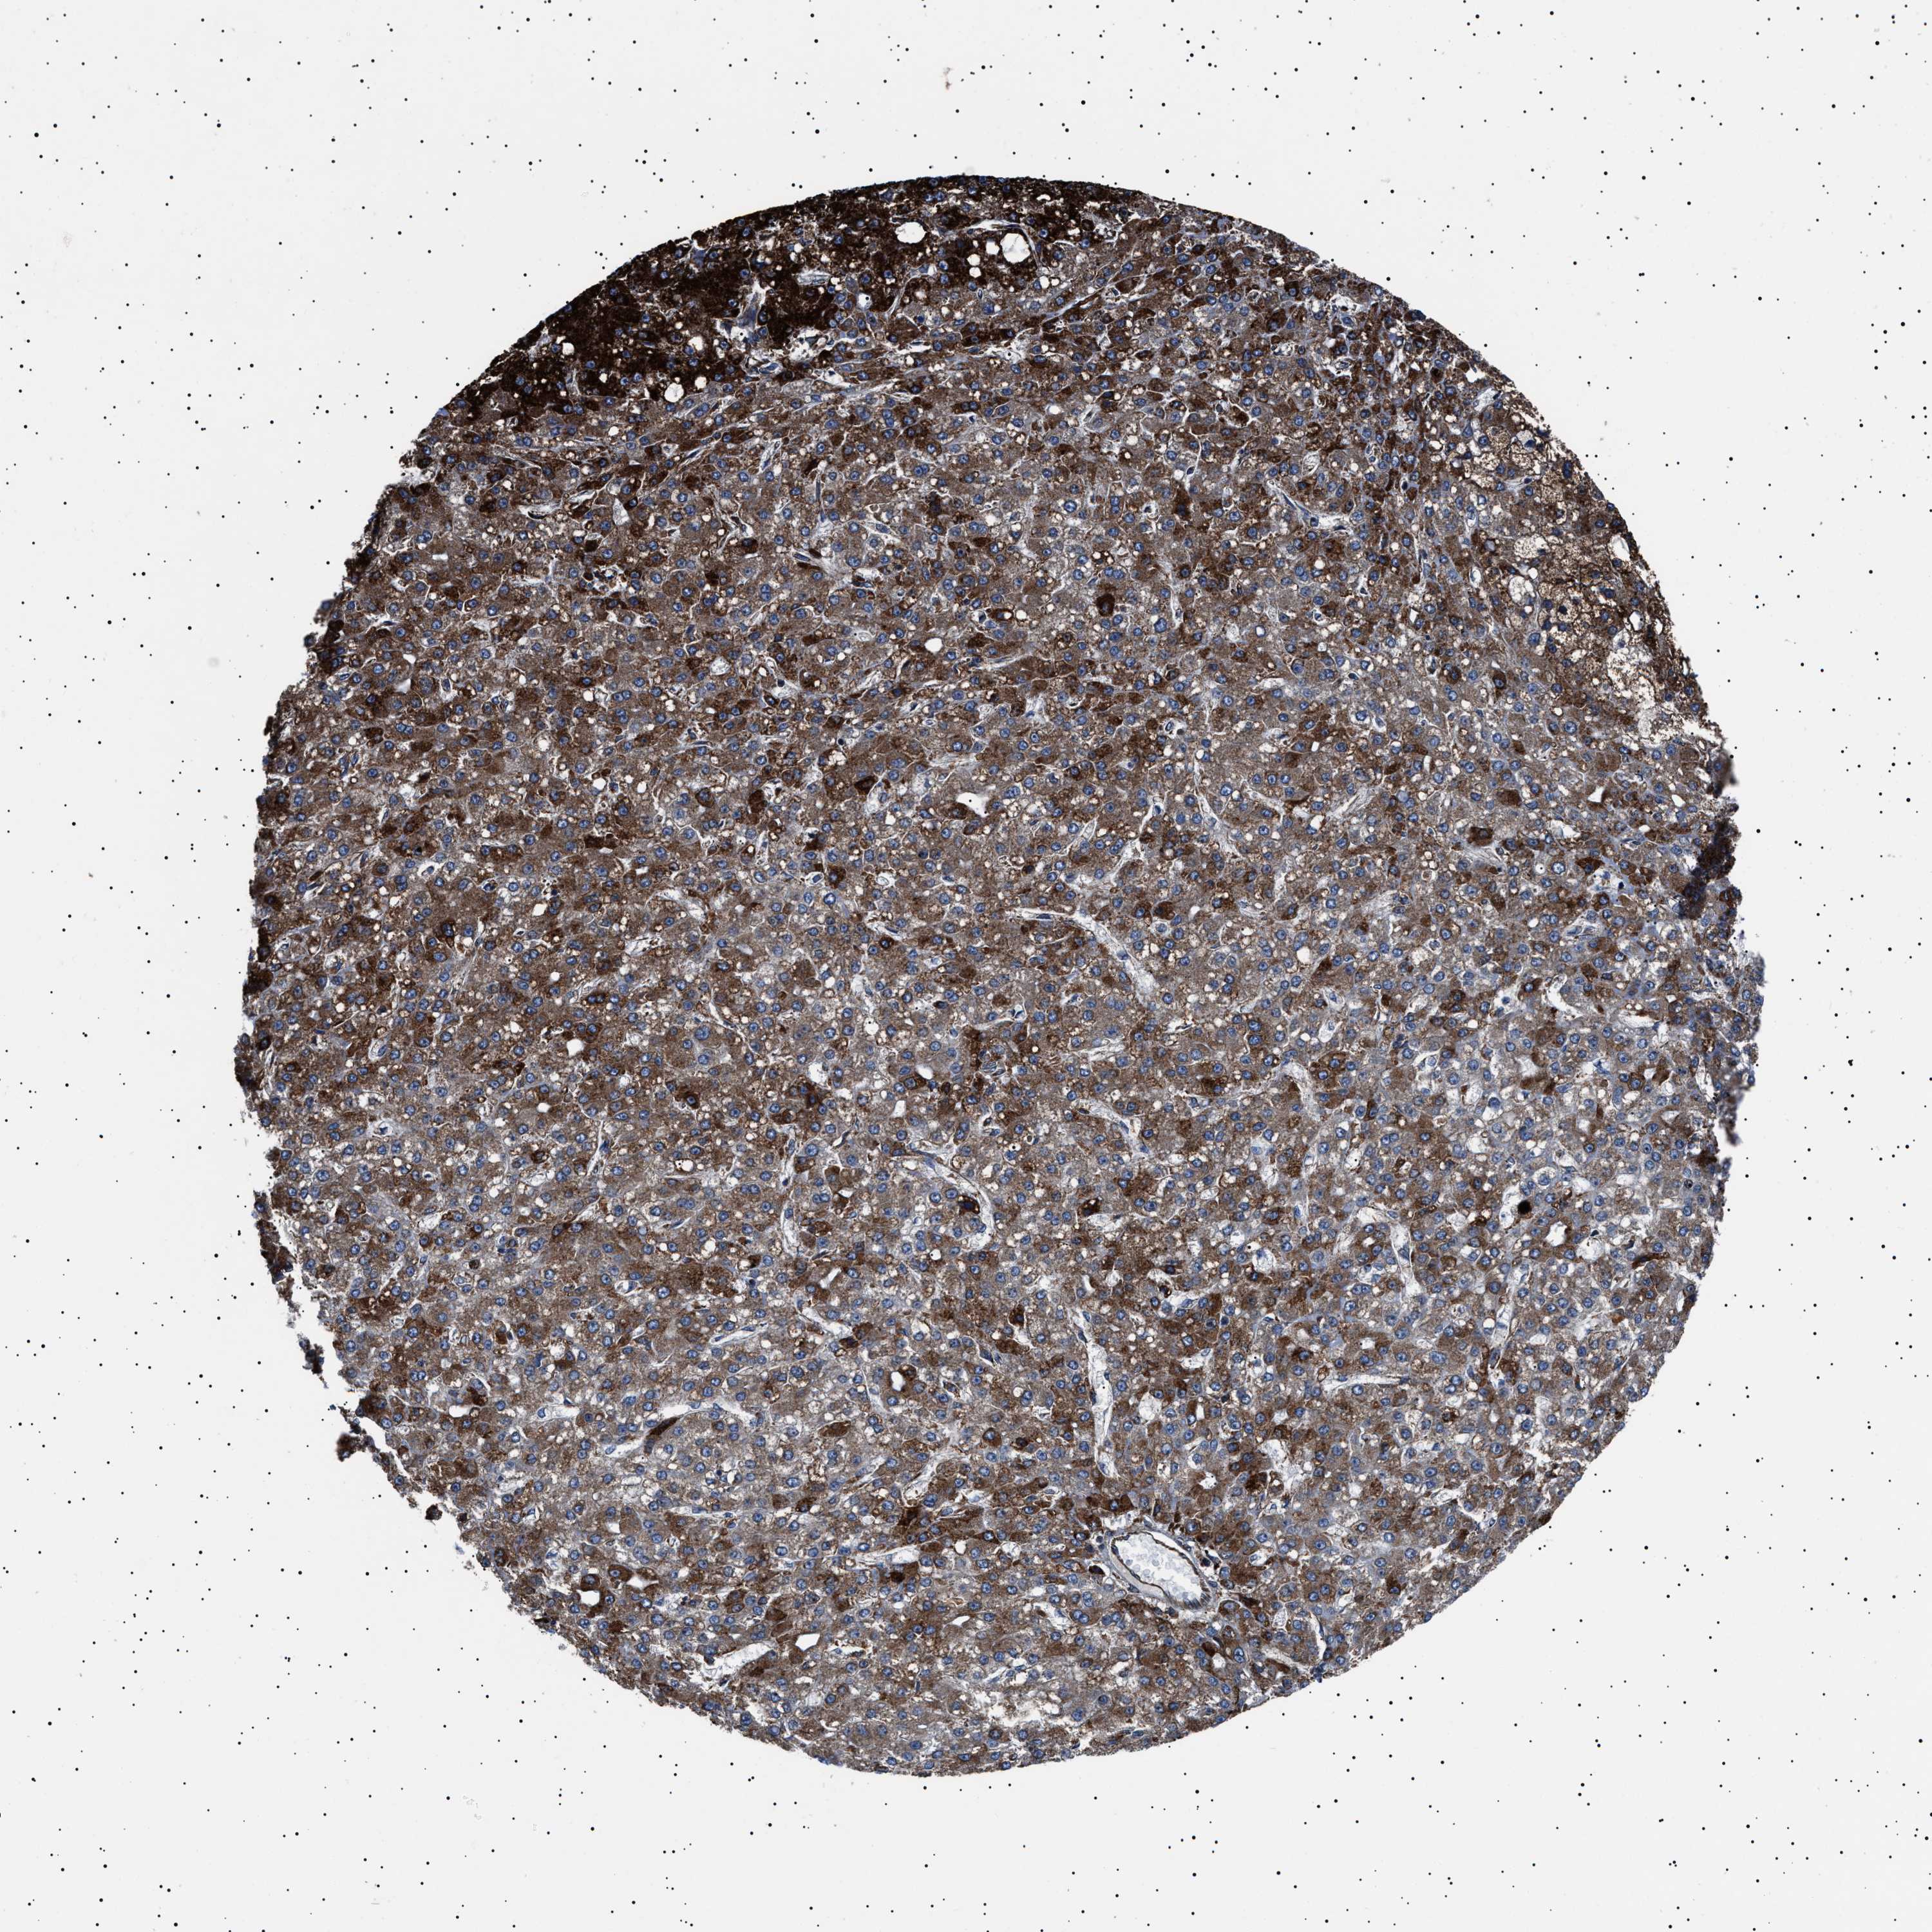

LIVER CANCER - Protein expressioni

A mouse-over function shows sample information and annotation data. Click on an image to view it in a full screen mode. Samples can be filtered based on level of antibody staining by selecting one or several of the following categories: high, medium, low and not detected. The assay and annotation is described here.

Note that samples used for immunohistochemistry by the Human Protein Atlas do not correspond to samples in the TCGA dataset.

Antibody stainingi

Antibody staining in the annotated cell types in the current human tissue is reported as not detected, low, medium, or high, based on conventional immunohistochemistry profiling in selected tissues. This score is based on the combination of the staining intensity and fraction of stained cells.

Each image is clickable and will lead to virtual microscopy that enables deeper exploration of all samples and also displays staining intensity scores, fraction scores and subcellular localization as well as patient and tissue information for each sample.

Antibody HPA001915

Antibody HPA021542

Staining

High

Medium

Low

Not detected

Intensity

Strong

Moderate

Weak

Negative

Quantity

>75%

75%-25%

<25%

None

Location

Nuclear

Cytoplasmic/membranous

Cytoplasmic/membranous,nuclear

Cholangiocarcinoma

Carcinoma, Hepatocellular, NOS